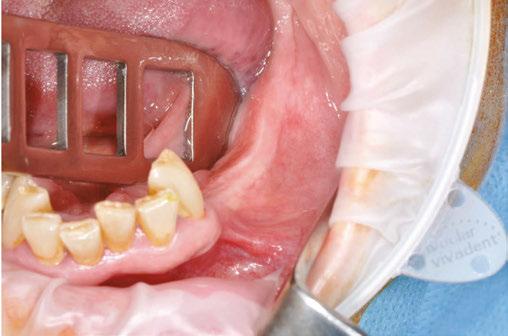

Our patient is consulting for pain in the right mandibular molar region and difficulty chewing (Figure 3).

Figures 2A and 2B: Panthera Dental platform interface; vestibular (2A) and lingual (2B) views of the subperiosteal implant Figure 3: Initial panoramic image Figures 4A-4C: Visualization of the subperiosteal implant in relation to the mock-up

not to undergo long and complex implant treatment. Her request is first and foremost functional. Esthetics and price are secondary concerns. We therefore offer the following treatment plan: keep the malpositioned anterior mandibular teeth with only mild gingivitis, rehabilitate the left posterior mandibular region with a subperiosteal implant, extract molars 47 and 48, and reassess the best implant solution for this region after healing.

Given the initial anatomical situation (strong resorption, significant mobile soft tissue, blockage by the tongue, V-shaped mandible), a conventional impression with a CIT and a physical mock-up with radiopaque markers are preferred.